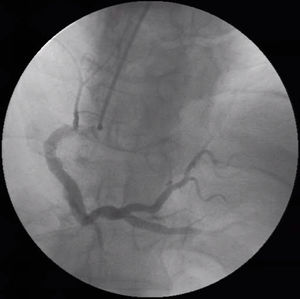

Case descriptionA 64-year-old male presented with exertional retrosternal pain. He had a past medical history of hypertension, dyslipidemia, obesity, bilateral carpal tunnel syndrome and underwent bilateral surgical release and cervical laminectomy. The resting electrocardiogram revealed an incomplete left bundle branch block, while the resting echocardiogram was completely unremarkable. He underwent a stress echocardiogram with dobutamine; at peak stress, the left ventricle developed regional wall motion abnormalities including hypokinesis of the inferior wall, associated with angina and soon followed by ventricular tachycardia, reversed with propranolol. The patient was hospitalized and underwent a coronary angiography which revealed slow flow, dominant right coronary artery with non-obstructive atherosclerosis and a left anterior descending artery (LAD) with intermediate lesions in mid and distal segments (Figures 1 and 2). A functional evaluation revealed a non-significant fractional flow reserve of 0.86 in the LAD, but a pathological CFR of 1.8 and an IMR of 61. Given the patient's symptoms, risk factors and diagnostic tests, he was considered to have microvascular angina and was treated with antiplatelet therapy, a statin, a calcium channel blocker and a transdermal nitrate, with symptomatic relief.